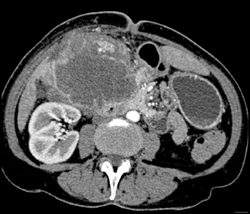

Gallbladder Cancer